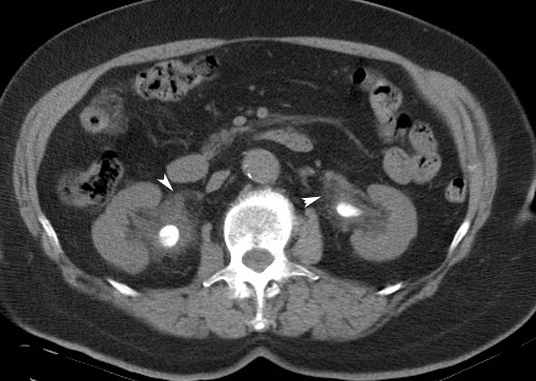

Bilateral Renal Pelvis Calculi

Arrowheads: There is soft tissue infiltration secondary to extravasation of urine around both renal pelvis.